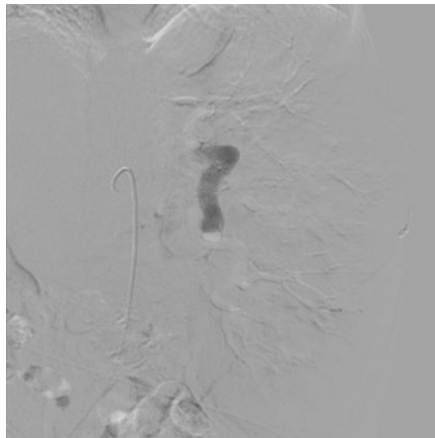

本刊推荐:为探讨脾动脉栓塞术(SAE)在Caroli综合征(CS)合并门静脉高压伴脾功能亢进患者中的治疗价值,研究人员开展病例研究。结果显示SAE可显著提升血小板计数(从29,000/μL升至394,000/μL),但术后出现发热、白细胞升高(WBC 19,000/μL)等栓塞后综合征。该研究为晚期Caroli综合征的并发症治疗提供了新思路,强调早期肝移植的重要性。